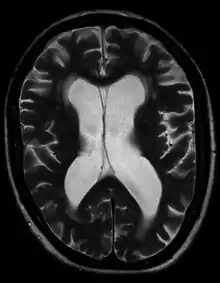

Hydrocephalus ex vacuo from vascular dementia as seen on MRI

• Normal pressure hydrocephalus (NPH) is a particular form of chronic communicating hydrocephalus, characterized by enlarged cerebral ventricles, with only intermittently elevated cerebrospinal fluid pressure. Characteristic triad of symptoms are; dementia, apraxic gait and urinary incontinence. The diagnosis of NPH can be established only with the help of continuous intraventricular pressure recordings (over 24 hours or even longer), since more often than not instant measurements yield normal pressure values. Dynamic compliance studies may be also helpful. Altered compliance (elasticity) of the ventricular walls, as well as increased viscosity of the cerebrospinal fluid, may play a role in the pathogenesis.

• Hydrocephalus ex vacuo also refers to an enlargement of cerebral ventricles and subarachnoid spaces, and is usually due to brain atrophy (as it occurs in dementias), post-traumatic brain injuries, and even in some psychiatric disorders, such as schizophrenia.[19] As opposed to hydrocephalus, this is a compensatory enlargement of the CSF-spaces in response to brain parenchyma loss; it is not the result of increased CSF pressure.[19]